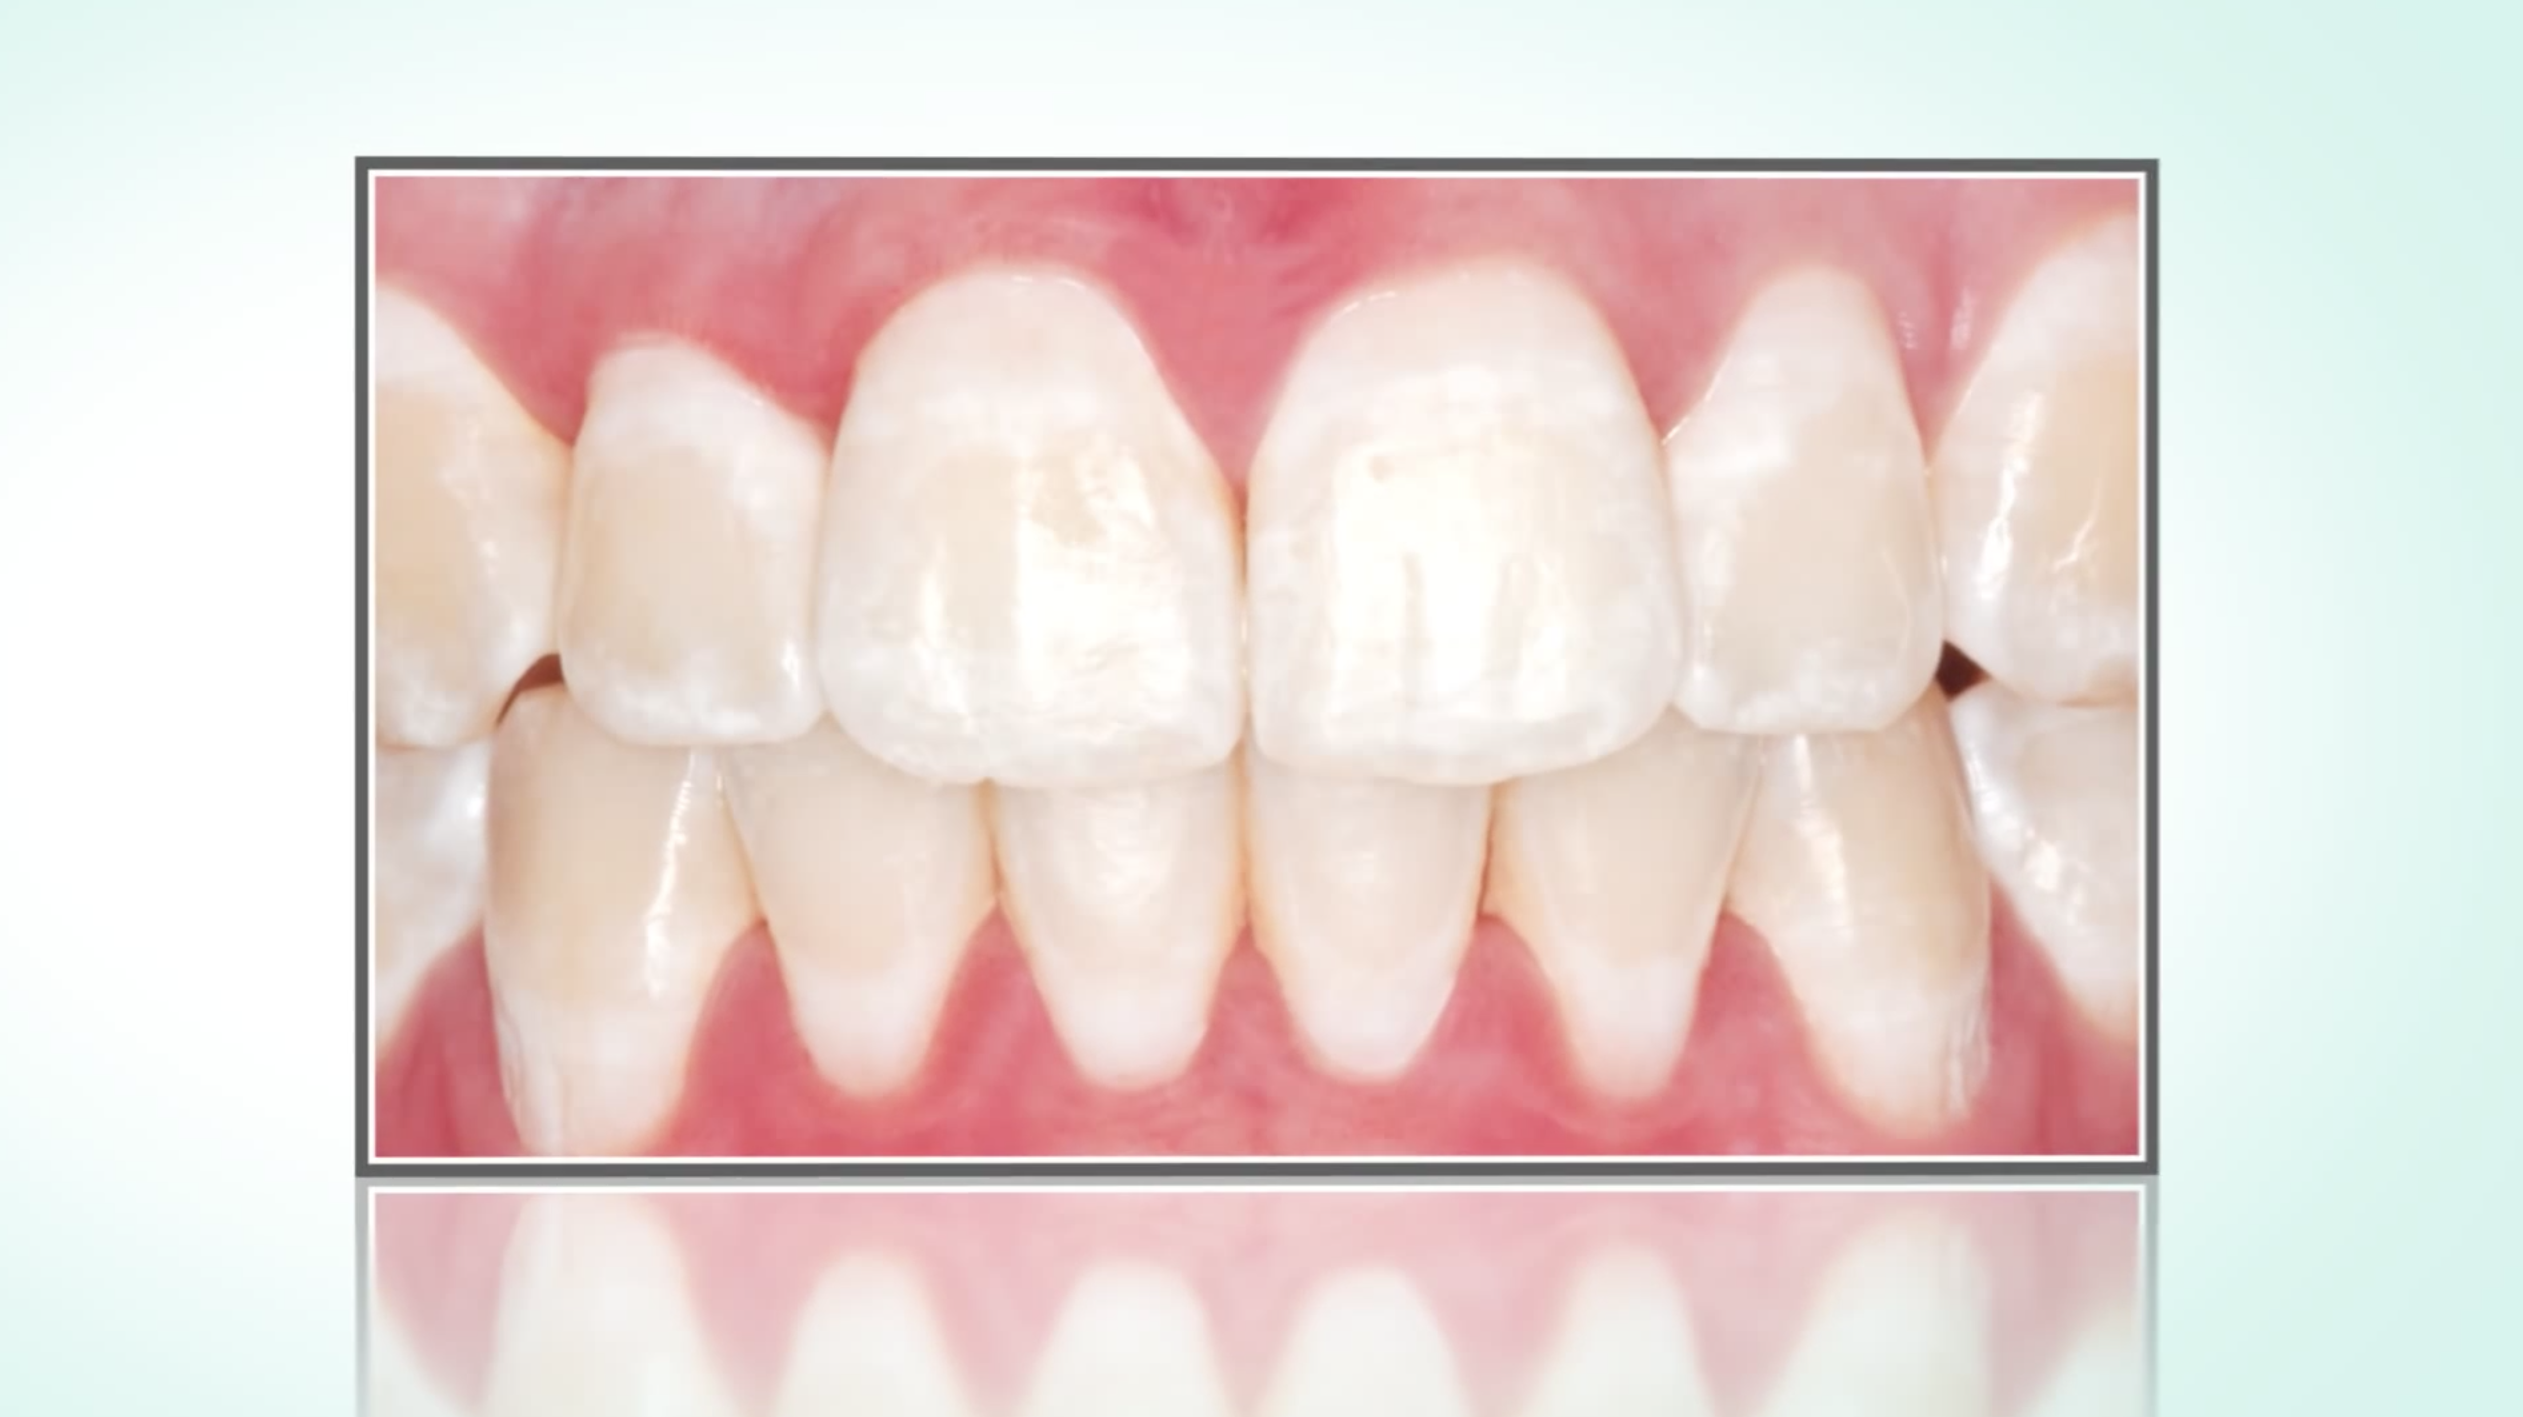

Caries infiltration

The so-called caries infiltration offers a completely new possibility to stop incipient caries early in just one session - without drilling and without sacrificing healthy tooth substance.

However, this is only possible for very small, incipient lesions.

The "infiltrant", a highly fluid plastic, penetrates into the porous enamel caries and seals the diffusion paths for cariogenic acids. Thus, the caries can be stopped early, in the interdental space as well as on smooth surfaces.

What to do in case of white stains on the teeth (fluorosis, after brackett removal, initial caries)